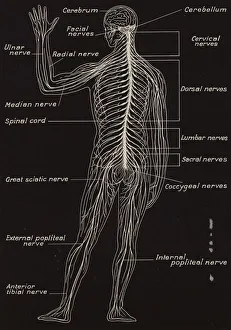

The central nervous system, the intricate network that governs our every thought and movement, is a marvel of complexity. From the delicate cerebellum tissue to the detailed light micrograph capturing its essence, we are reminded of its importance in maintaining balance and coordination. Anatomy comes alive as we explore the human brain from an inferior view. The intricacy of brain fibers is revealed through DTI MRI scans like C017/7099 and C017/7035, showcasing their vital role in transmitting information throughout this extraordinary organ. Artistic renderings bring us closer to understanding the medulla oblongata's significance within the brain. Its portrayal in various artworks allows us to appreciate how it controls essential functions such as breathing and heart rate. As we delve deeper into studying the central nervous system, models of the human brain provide invaluable insights into its structure and organization. Lateral views reveal countless regions responsible for cognition, emotion regulation, sensory perception, and motor control. Microscope slides offer glimpses into nerve cells' intricate architecture—a testament to their ability to transmit electrical signals at lightning speed. Meanwhile, glial stem cell cultures captured under a light microscope remind us of their crucial role in supporting neuronal function. Finally, artistic representations unveil the limbic system's enigmatic nature—an interconnected web responsible for emotions and memory formation. These captivating artworks allow us to visualize this complex network within our brains. Exploring these hints provides a glimpse into the awe-inspiring world of our central nervous system—the very foundation upon which our thoughts, actions, memories reside—reminding us just how remarkable our brains truly are.